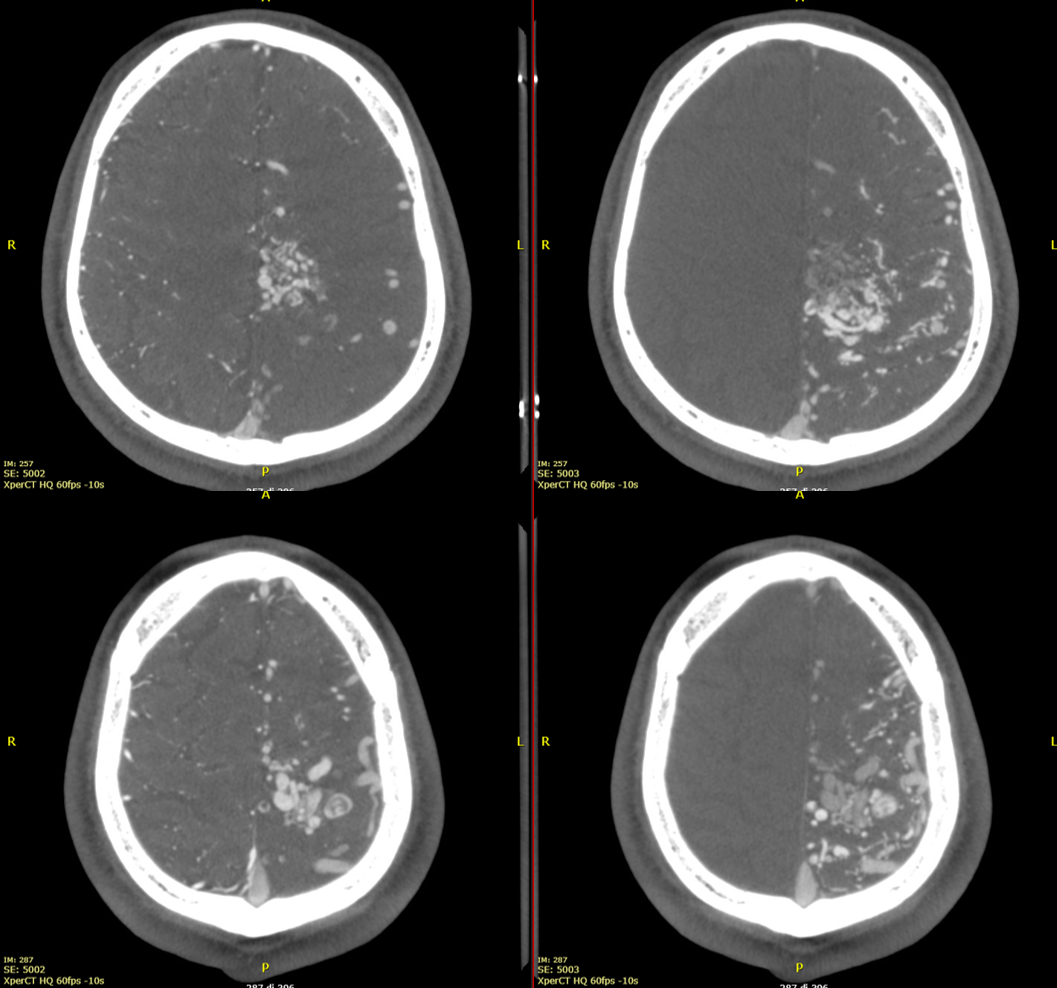

This is an Xper-CT acquisition done with the 48 cm FOV, HR 60 fps, 10-seconds protocol. We manually injected 30 ml of 50% contrast media (250 mg/ml), with a 30 ml syringe, beginning the injection 4-5 seconds before starting the acquisition.

The first pass to have good Xper-CT images for GammaKnife is a new reconstruction with 100% FOV, stent protocol, and 5123 resolution. The reconstruction must include the whole head.

Images will be sharper and with better contrast resolution.